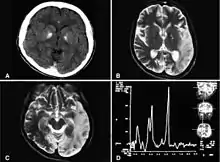

التشخيص

- الرنين المغناطيسي على المخ .

- أخذ عينة من المخ : تظهر تبدلات شبيهة بتلك الناجمة عن النشبة (سكتة) .